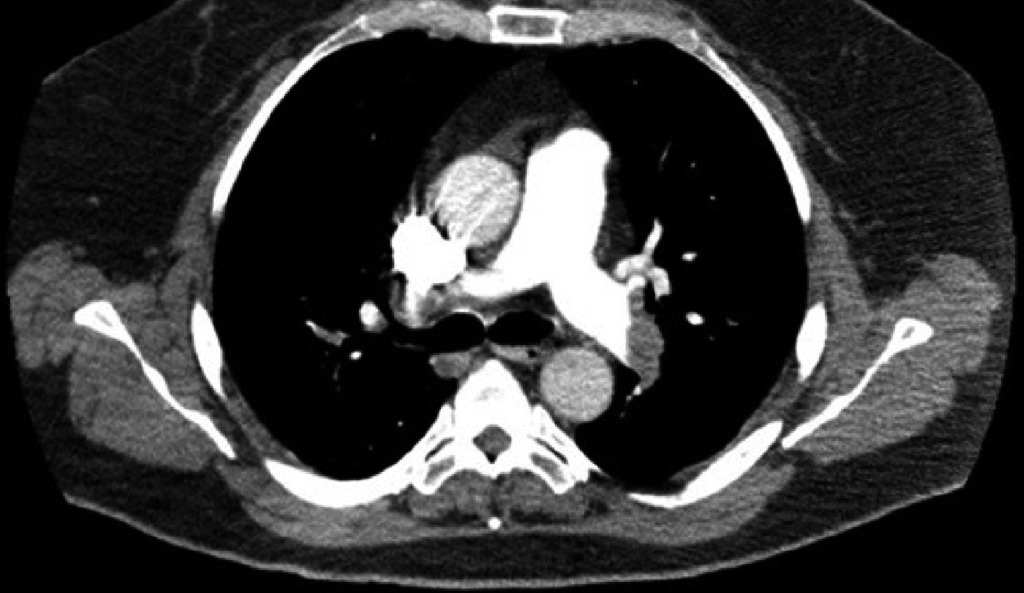

A los 40 días de finalizar la radioterapia comienza con disnea súbita sin otra clínica acompañante. La saturación de oxígeno es del 91%, con una gasometría que muestra hipoxemia. Se realiza una angio-TC torácica que confirma un tromboembolismo pulmonar en las arterias pulmonares distales derecha e izquierda con dilatación de la arteria pulmonar principal (Figura 2). No se constata trombosis venosa profunda ni a la exploración ni mediante ecografía Doppler de ambas extremidades inferiores.